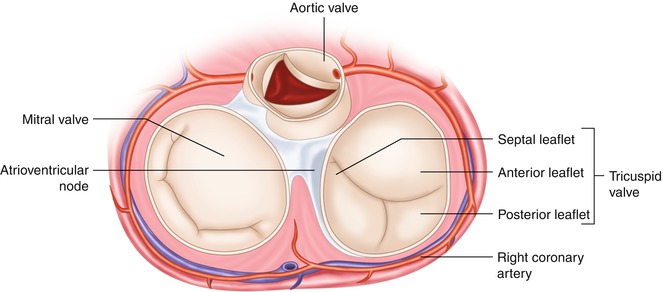

The tricuspid valve consists of three flaps or leaflets however cases are found when the tricuspid valve consists of only two or even four leaflets instead of the traditional three. The tricuspid valve lies within the right trigone.

The space in between the septal insertion of the tricuspid valve and the septal insertion of the anterior leaflet of mitral valve belongs to the membranous septum that separates the left ventricle from the right atrium.

Tricuspid valve anatomy. An appreciation of the complex and variable anatomy of the tricuspid valve is essential to unraveling the pathophysiology of tricuspid regurgitation. It is the atrioventricular valve that allows blood to flow from the right atrium to the right ventricle. Then blood exits the heart via the pulmonary artery.

Anatomy of the tricuspid valve. The tricuspid valve complex consists of the annulus leaflets right ventricle papillary muscles and chordae tendinae. Right atrioventricular valve tricuspid valve these are large veins that transport deoxygenated blood from the body back to the heart.

A greater appreciation of normal and abnormal anatomy is important as new methods of treating the tricuspid regurgitation are developed. It opens during diastole and closes during systole. The tricuspid valve tv is a complex structure.

B the relevant anatomy shown from the front view. The tricuspid valve lies between the right atrium and the right ventricle and is placed in a more apical position than the mitral valve. The tricuspid valve has an area of 4 to 6 cm square and is located between the right atrium and the right ventricle of the heart.

The valve has anterior posterior and septal leaflets cusps the bases of which attached around the av orifice to the fibrous ring fibrous skeleton of the heart. Blood collects within the right atrium and it must flow through the tricuspid valve in order to enter the right ventricle. The tricuspid valve functions as a one way valve that closes during ventricular systole to prevent regurgitation of blood from the right ventricle back into the right atrium.

A the anatomy of the tricuspid valve and adjacent structures from a surgical view. Anatomy of the tricuspid valve. The tricuspid valve anatomy shows greater variability than the anatomy of the mitral valve.

In normal heart the tricuspid valve is located slightly closer to the apex than the mitral valve. The red dotted lines show the direction of dilation of various structures in the setting of secondary tricuspid regurgitation. Unlike the aortic and mitral valve it is not possible to visualize all tv leaflets simultaneously in one cross sectional view by standard two dimensional echocardiography 2de either transthoracic or transesophageal due to the position of tv in the far field.

It opens during ventricular diastole allowing blood to flow from the right atrium into the right ventricle.